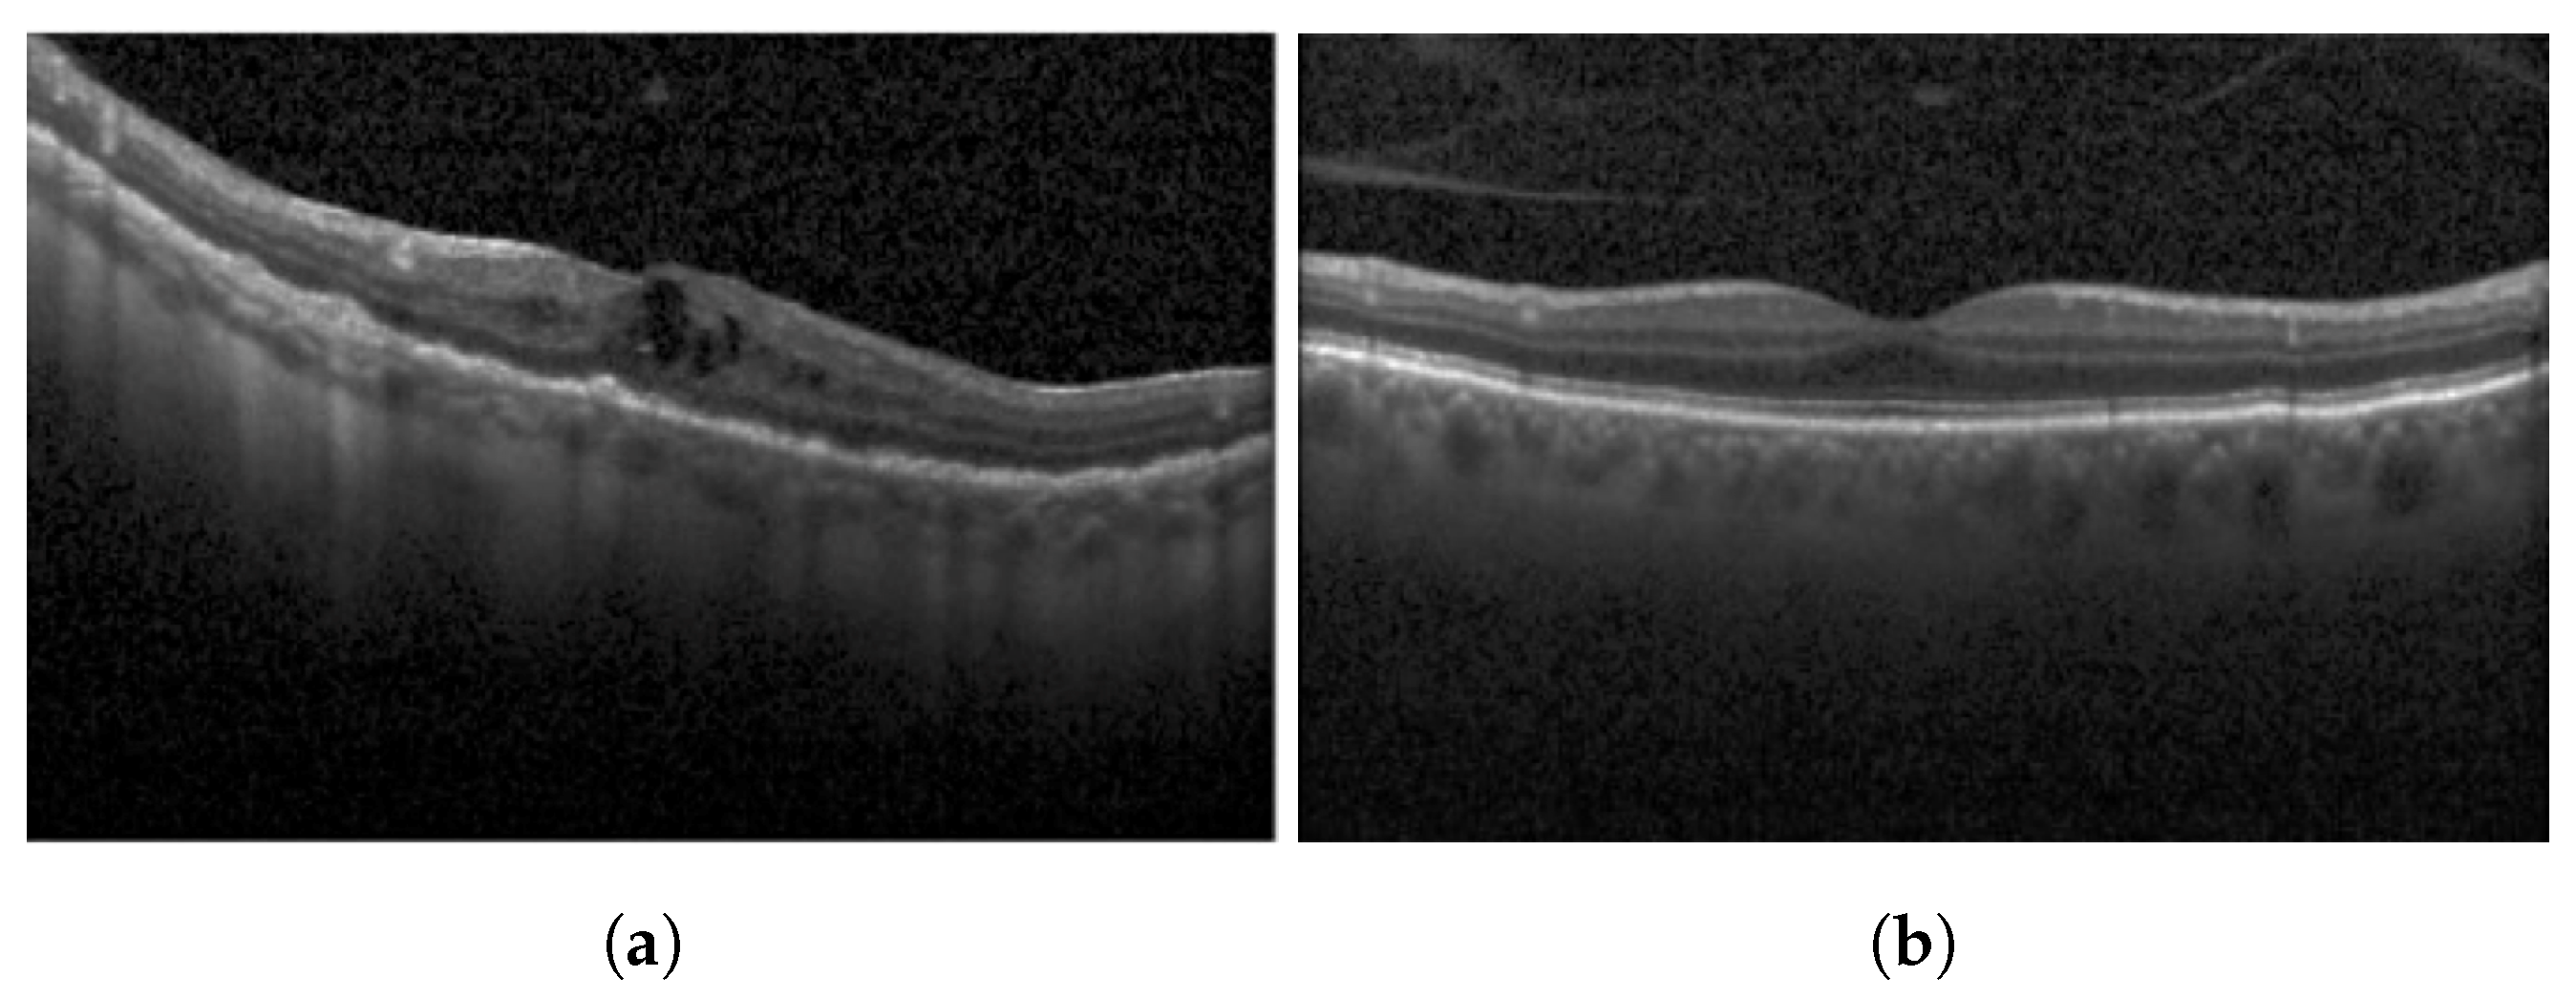

2.1. Disorganization of Retinal Inner Layers (DRIL)

3.1.1. Disorganization of Retinal Inner Layers (DRIL)